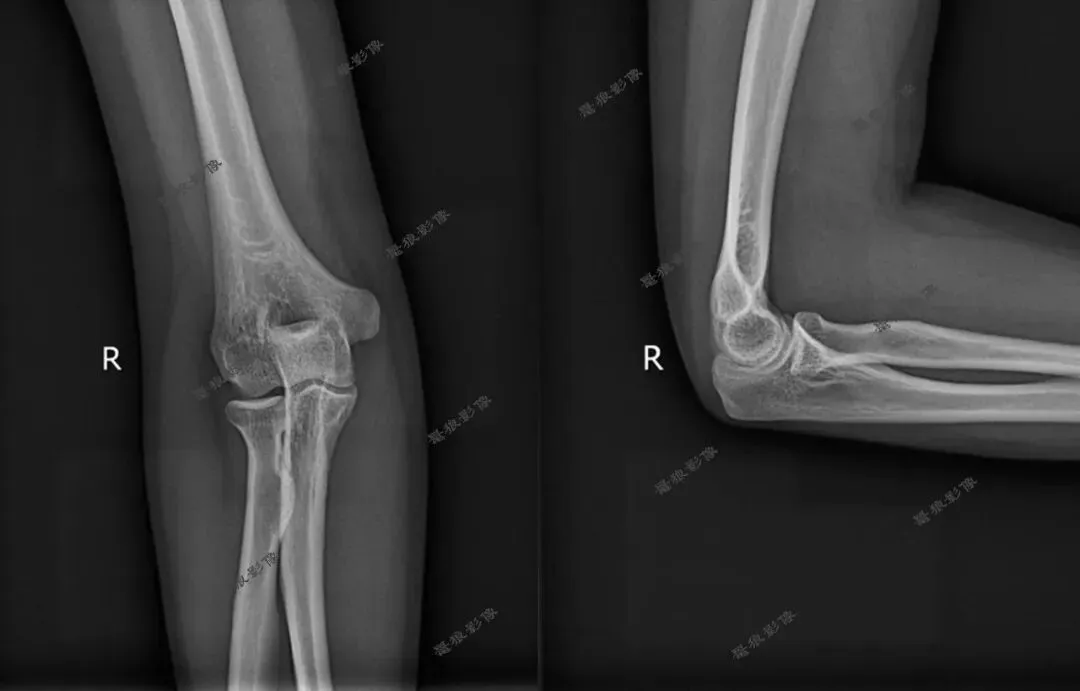

我们再看肘关节几组图片

七、需要警惕以下情况发生